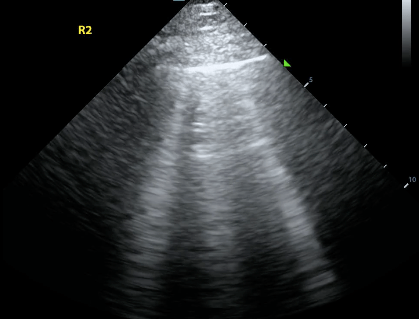

Name of this ultrasound finding of the heart.

What is a cardiac myxoma?